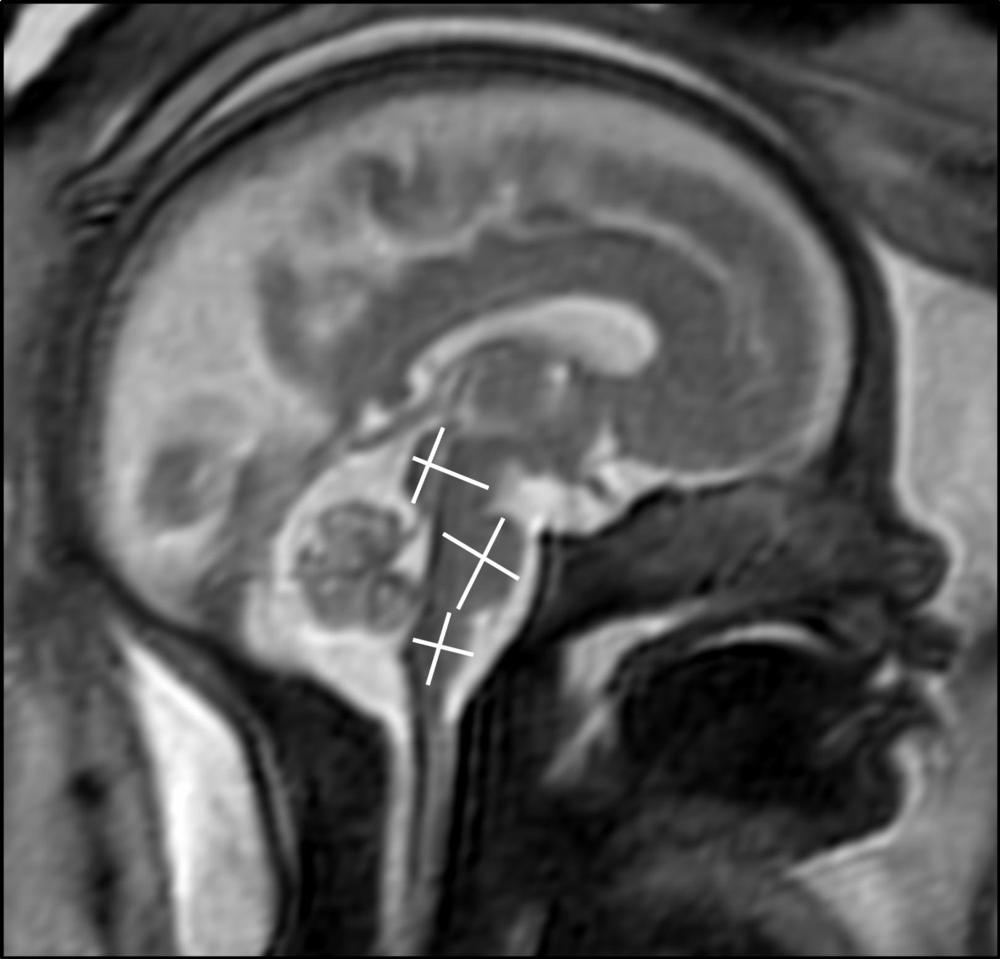

Two board-certified radiologists with several years of experience in fetal MRI evaluated the scans. They found that the brain development in the assessed areas was age-appropriate in all fetuses. There were no findings indicative of infection of the fetal brain.

Figure 1. MRI of fetal brain development.